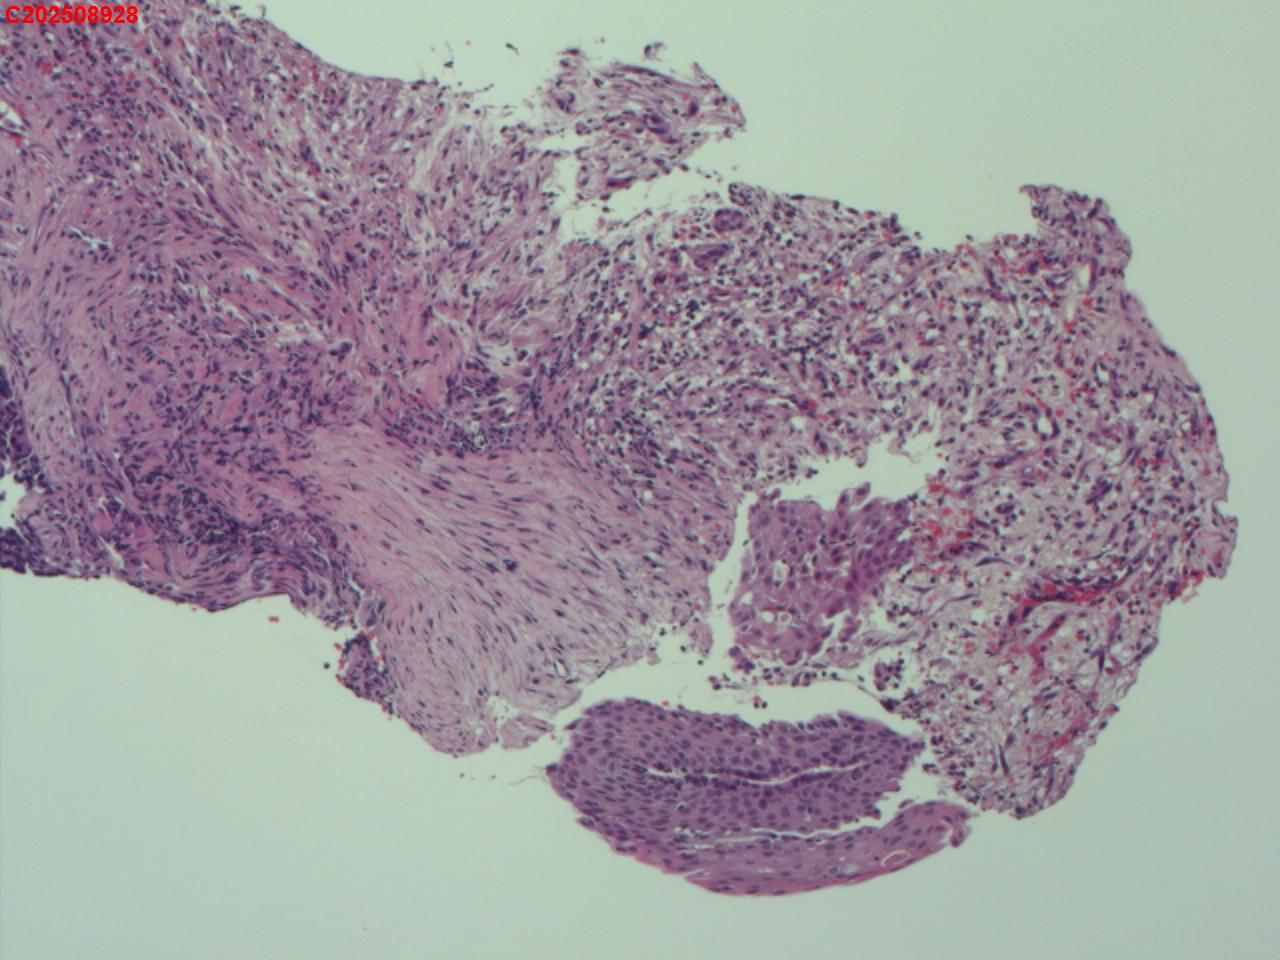

喉部右侧、声带下方咬检

男

56岁

喉Ca?

咳嗽

喉室内右侧声带下方新生物。

考虑鳞癌

鳞癌,有微浸润